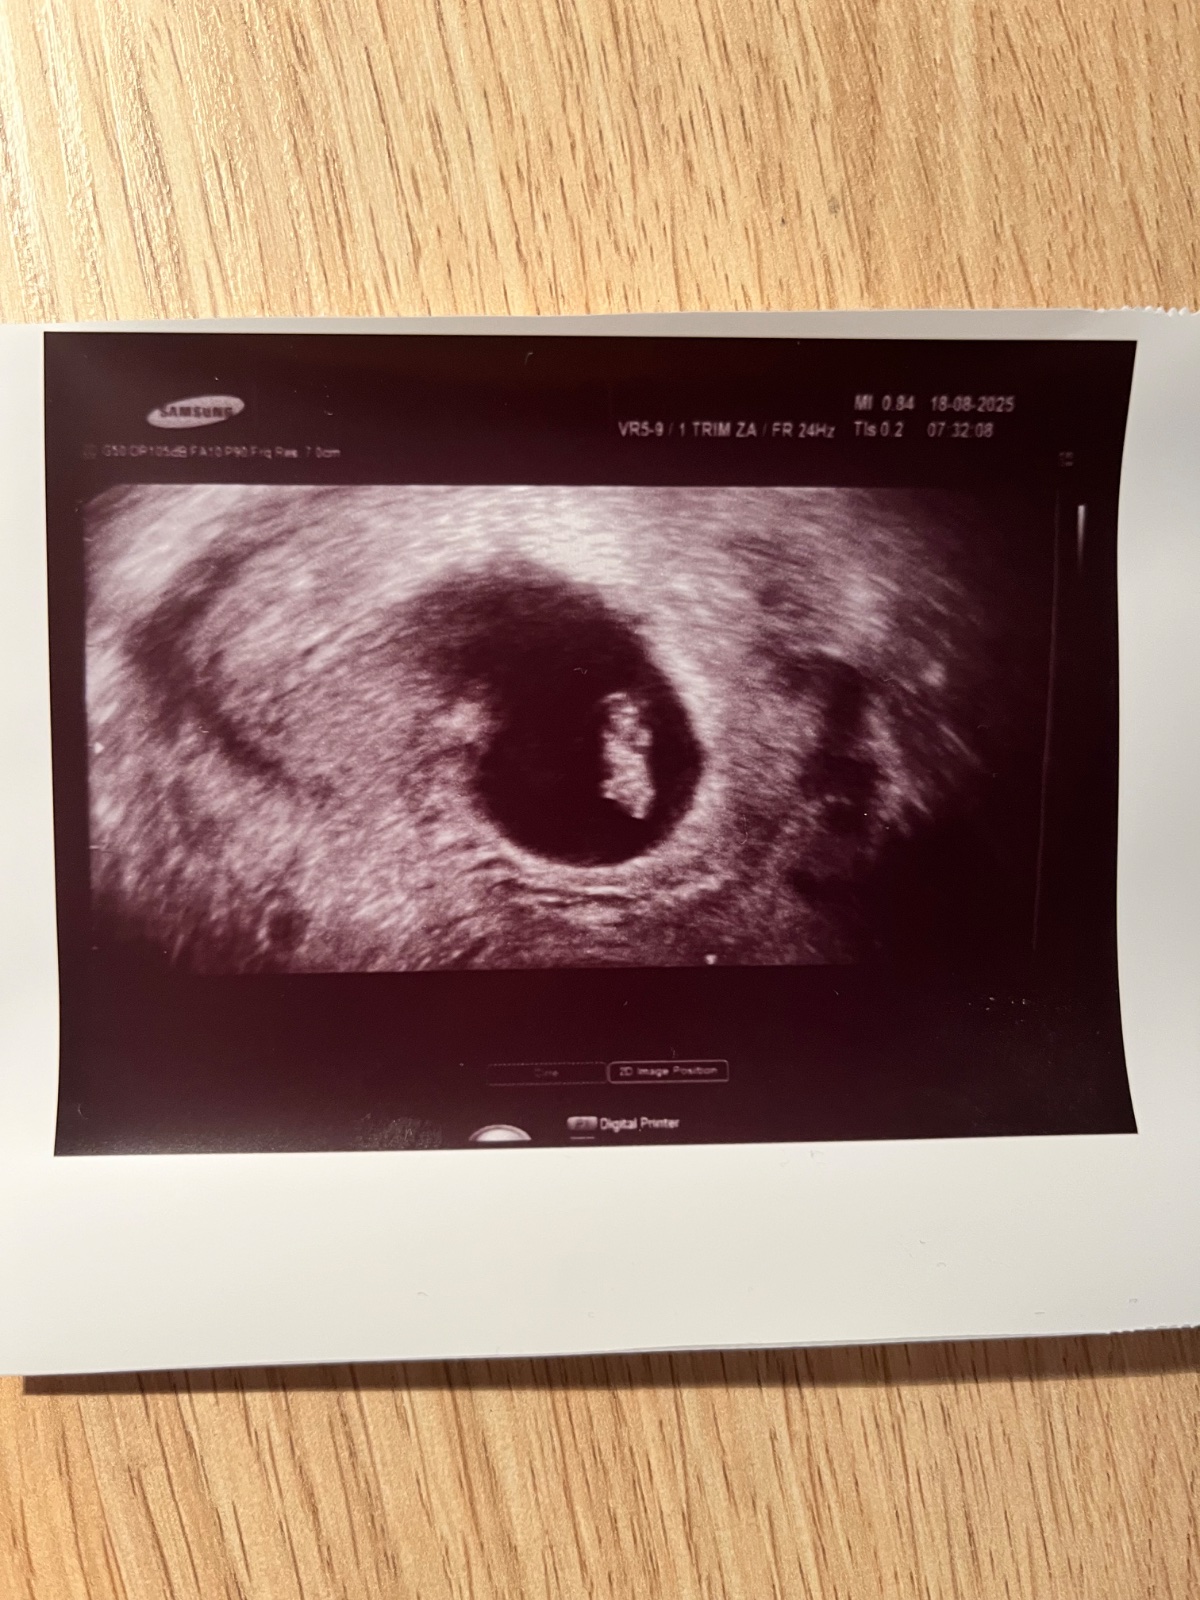

Kde je žĺtkový vak na ultrazvukovom snímku?

@anonym_autor Ta čierna machula by mala byť gestacny vak a to biele v čiernej machuli je plod. Predpokladám, že srdiečko už bolo viditeľné tiež. Gratulujem ;)

@tinka_1807 áno, bolo aj srdiečko. Plod vidím, ale neviem to identifikovať, čo je čo...

@anonym_autor Bábo je ešte malinké na identifikáciu kde je čo. Ešte sa to vyvíja. Cca v 10 týždni už to bude jasnejšie ;)

Ešte dodám, je to 7+4 tt